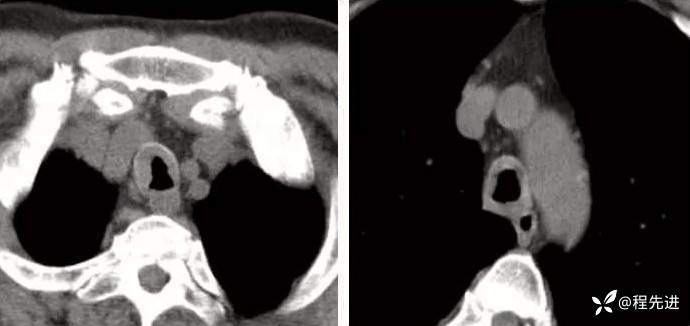

病例三:

看图说话